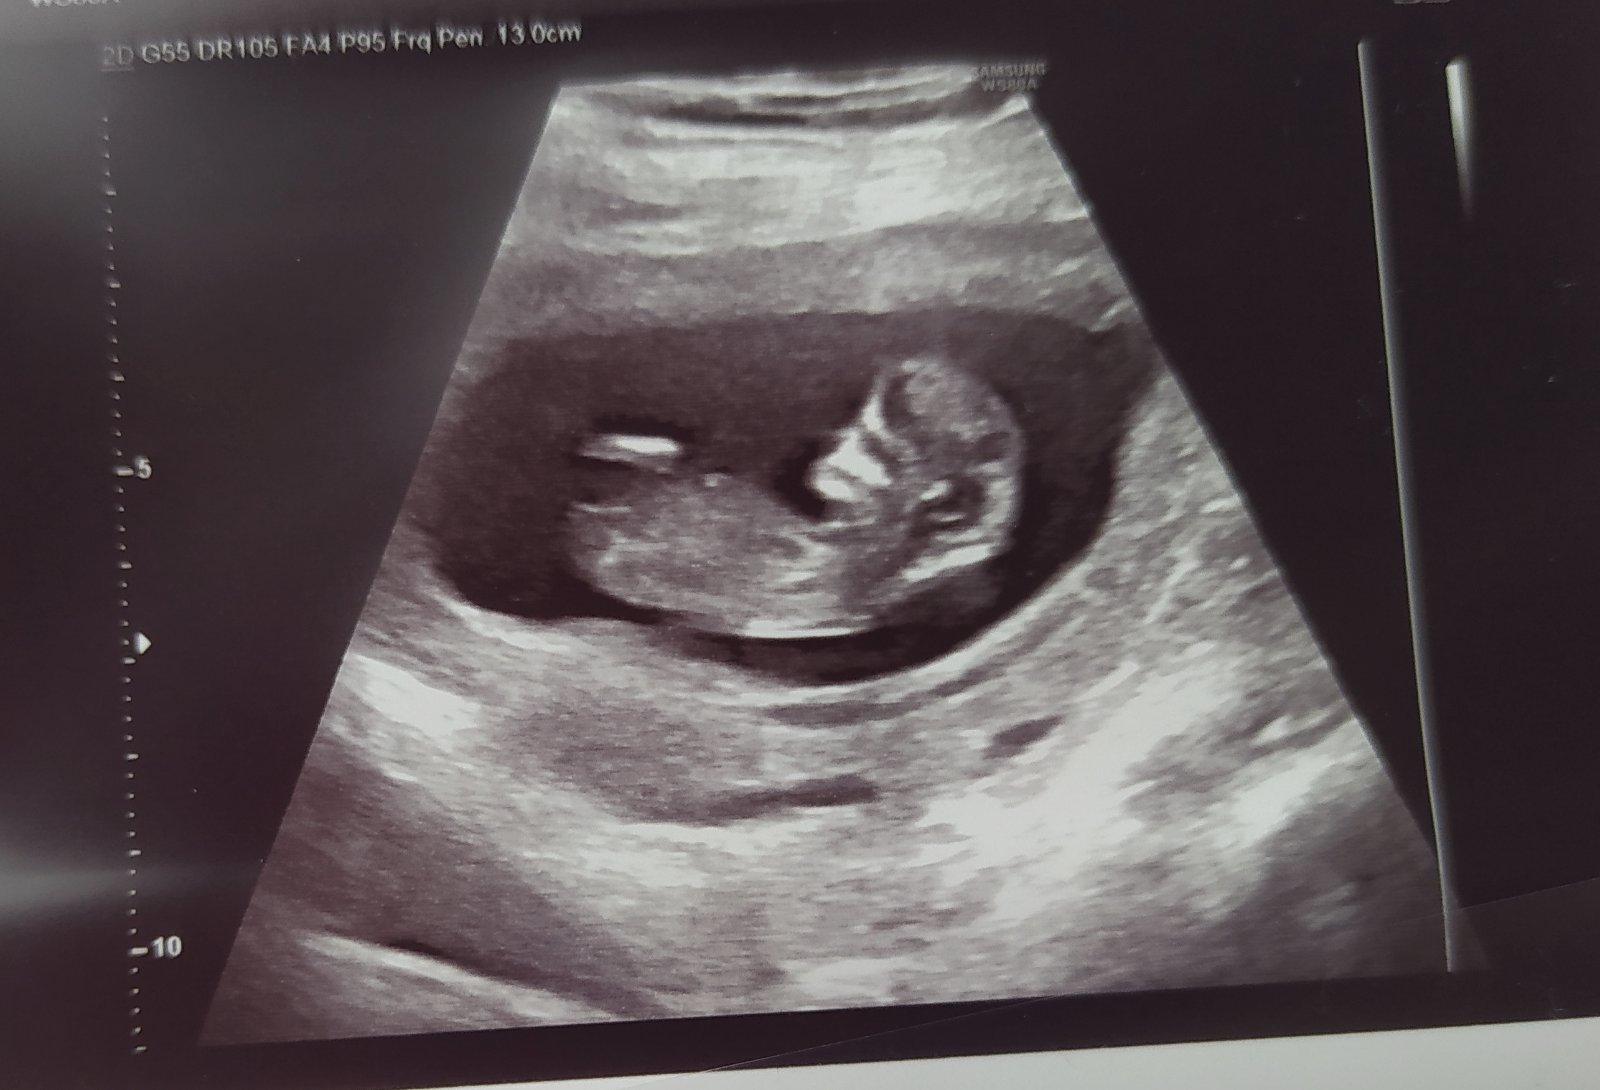

Ahojte 😊 Tak já se hlásím v 11+3(4), za týden jdu na první screening a miminko už zamávalo a "plivlo" bublinku. No málem jsem řvala jako malá 😁😍

Taky jsem včera byla 🙂 mimi roste, 14cm, srdíčko v pořádku 🙂 21.10. Screening, to jde se mnou i manžel 🙂 termín nám zůstal na 2.5.21. Začínám na 68kg 😳

@adelafri no, prý odpovídá na 15tt, ale já to v červenci jeste měla. Tak na screeningu se prý premeri pořádně. Holky, ať vám to dobře dopadne 😘😘

@cvachna já měla minulý týden 8cm a to jsem byla 10+5.

Mě doktor vysvětloval, že tyhle cm (jako mám napsané na fotce) nejsou cm plodu. Plod kolem 12tt má 5cm (více opravdu není možné, natož 2x-3x tolik).